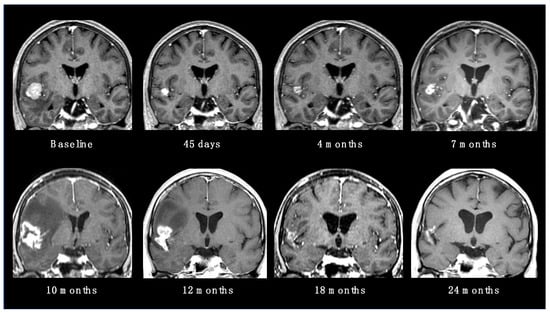

2.4. SRS Reirradiation